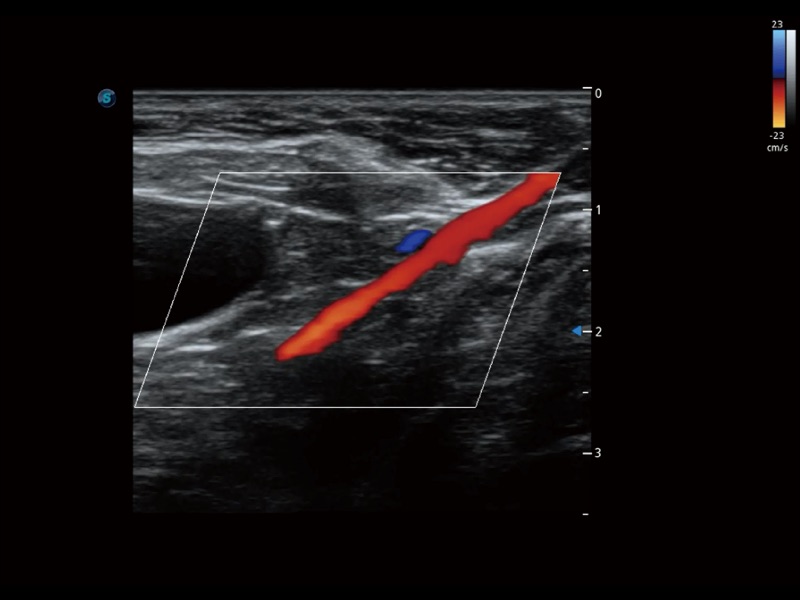

通过创新的 Matrix E自适应滤波器和超长时间域算法,极大提升超低速微细血流的检出能力,同时更精准地滤除软组织和噪声信号,为兽用医生提供以往无法通过常规血流获得的疾病诊断信息。